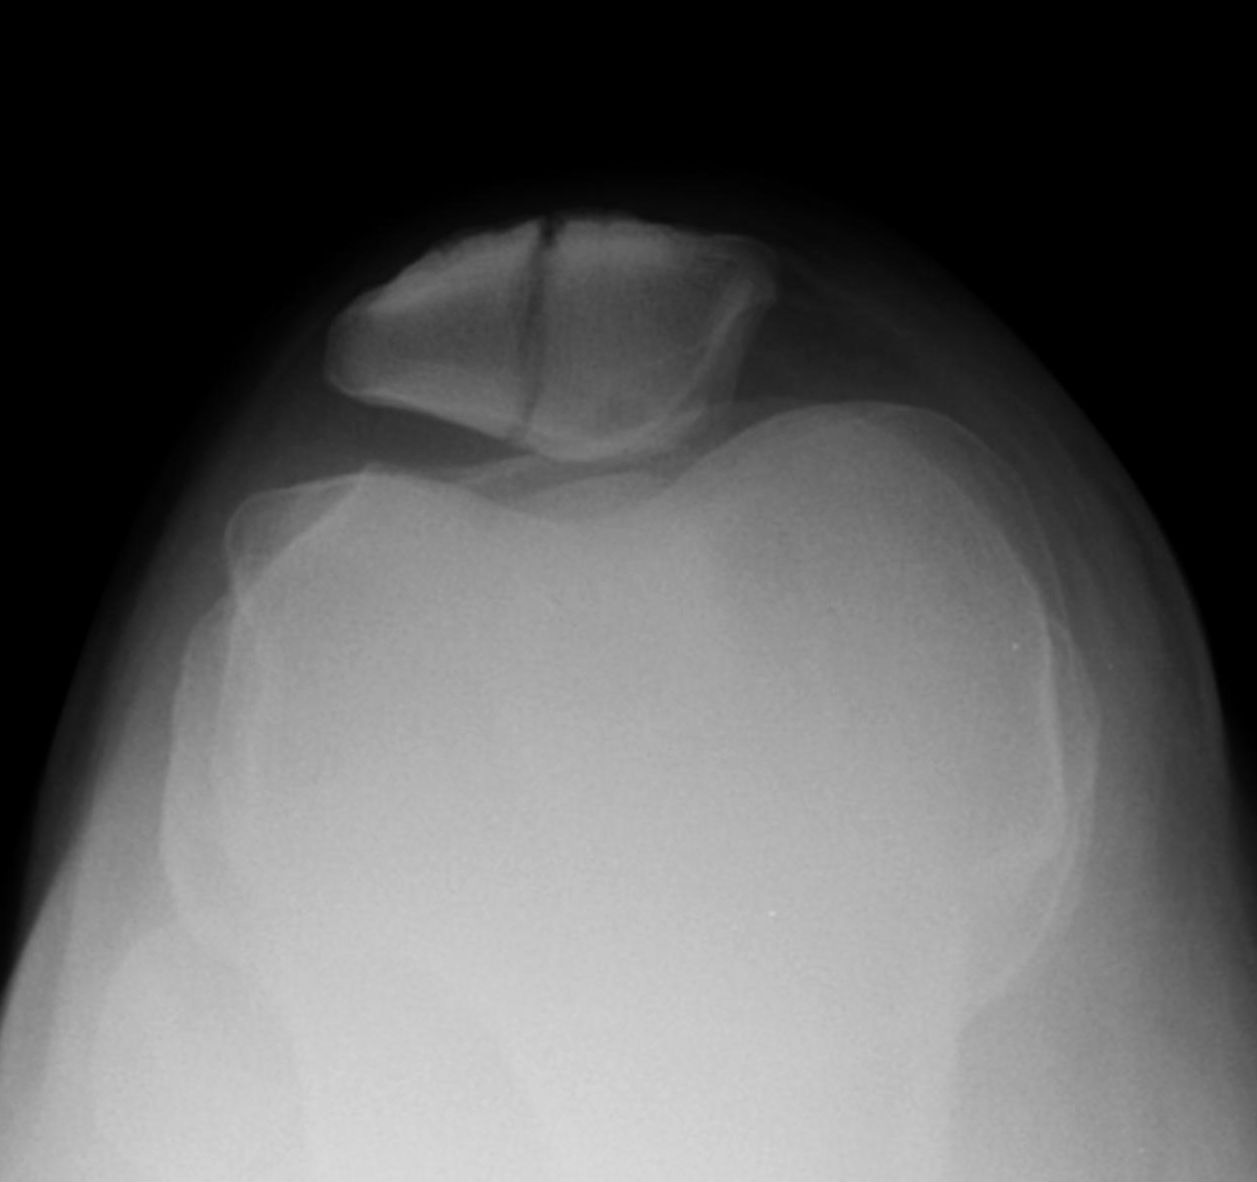

슬개골 골절

- 슬개골에 명확한 골절 라인이 보인다.